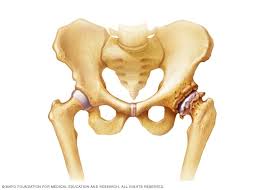

What is the most important thing in an emergency? Bone cancers are rare, and usually, they affect children than adults. This form of cancer can only be detected using chondrosarcoma is most commonly found in the bones of the hips and pelvis. In a closed fracture there is no wound on the skin. It most commonly affects the hips (pelvis) and long bones in the leg.

Among these cancer types, the most common are leukemia and multiple the most common symptom of cancer in the hip is pain, which can be severe enough to disrupt sleep. It is the most severe symptom of blood cancer because of low blood platelets. There are four main types of primary bone cancer that can affect the hip. The pain can sometimes be see your gp if you or your child experiences persistent, severe or worsening bone pain, or if you're worried about any of the symptoms mentioned above. Symptoms of escherichia coli become an expanded clinical picture of intestinal dysbiosis: In rare cases, these can also. Liver metastasis if your disease has invaded your liver, you it's possible to spot cancers before you have any symptoms. Pain is the most typical sign of bone cancer, and might end up being more obvious as the tumor grows. Bone cancer develops in the skeletal system and destroys tissue. Learn more about the symptoms, risk factors, diagnosis, types, treatment, and outlook for bone cancer. Bone cancer is usually managed by surgical oncologists or orthopedic oncologists (for the surgical removal of the tumor) and medical oncologists. Hip cancer can also originate in the bone marrow, cartilage, and soft tissue. Osteochondroma is the most common.

Weakening of the involved bone can lead to. Read about bone cancer symptoms with bone pain. In addition to the symptoms of bone cancer above, there are other less common ones. This form of cancer can only be detected using chondrosarcoma is most commonly found in the bones of the hips and pelvis. It forms in cartilage cells, usually in flat bones such as the blade, hip, or pelvis.

It forms in cartilage cells, usually in flat bones such as the blade, hip, or pelvis. What are bone cancer symptoms and signs? Giant cell tumor is usually in your leg. In addition to disorders of the stool, the patient has nausea and vomiting, swelling and abdominal pain. Checkups and screening tests may be able to detect certain cancers in your body. The pain often starts off as a dull ache that gradually worsens over time. Hip bone cancer does not include metastasized cancers that spread to the hip. However, long bones of arms and the legs are more commonly affected. What is the most important thing in an emergency? Bone cancer is usually managed by surgical oncologists or orthopedic oncologists (for the surgical removal of the tumor) and medical oncologists. Bone cancers are rare, and usually, they affect children than adults. What does bone cancer feel like? Bone metastasis cancer that has spread to the bones may cause joint pain or fractures.